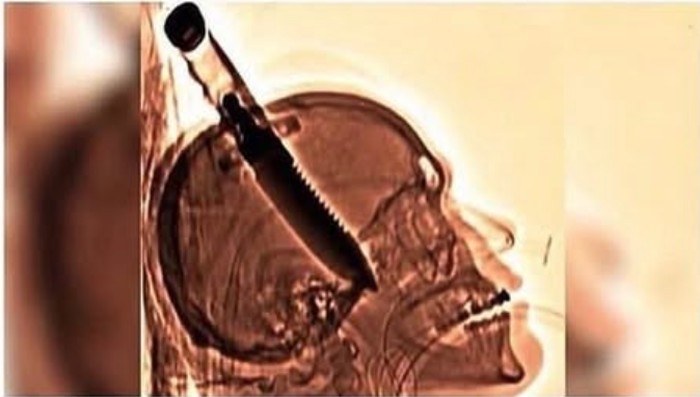

Pada tahun 1998, Michael Hill ditikam di tengkoraknya, oleh orang tak dikenal, dengan pisau besar untuk bertahan hidup ketika dia membukakan pintu di rumah temannya. Dia bertahan hidup bahkan tanpa infeksi dan mendapatkan kembali kesadaran dan seluruh fungsi tubuhnya dalam waktu seminggu, meskipun pisau tersebut telah menyebabkan kerusakan permanen pada ingatannya dan melumpuhkan tangan kirinya. Foto: Boredpanda